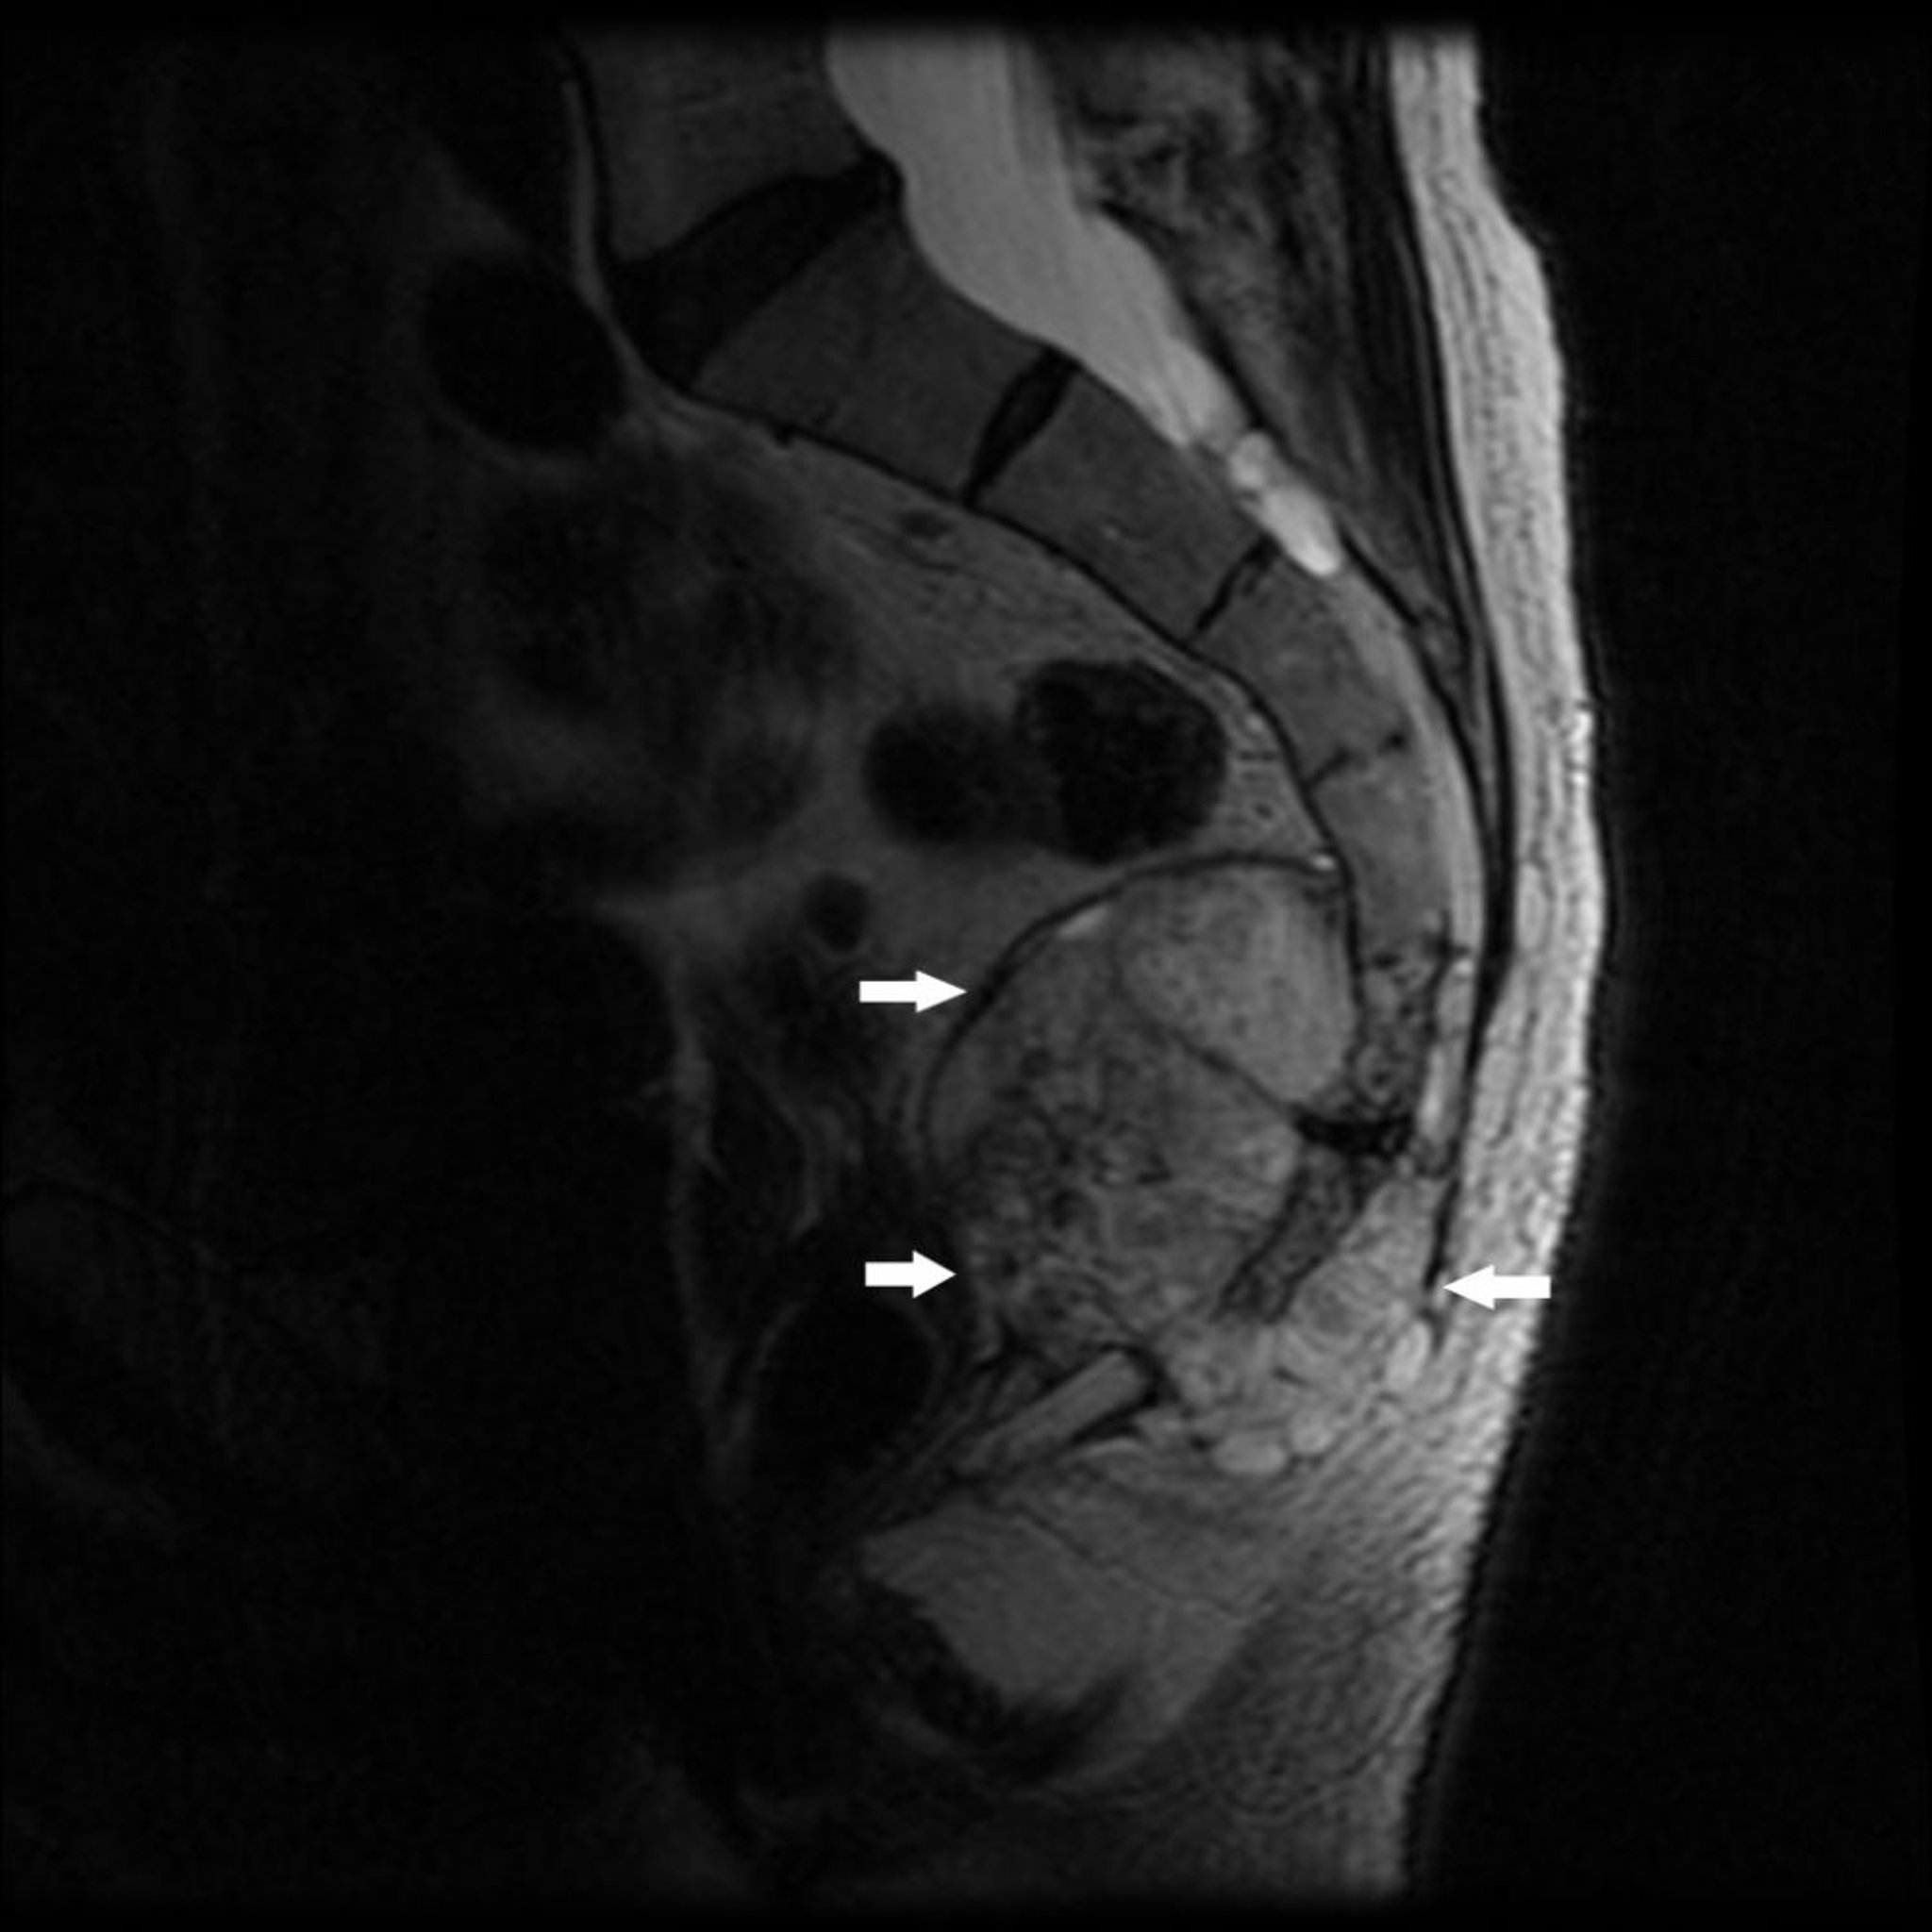

На данном снимке МРТ показана опухоль в каудальном отделе крестца (S4) и копчика с разрушением костной ткани и мягкотканным образованием (стрелки), типичными для хордомы.

Image courtesy of Michael J. Joyce, MD, and Hakan Ilaslan, MD.